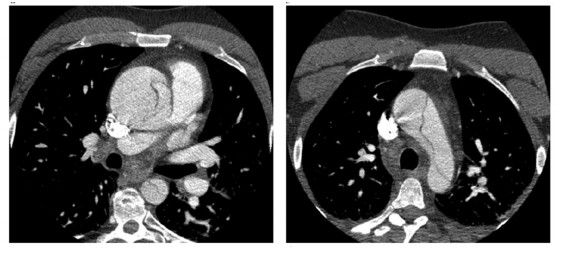

Foi admitido na UTI um paciente masculino de 53 anos devido à dor torácica de forte

intensidade, dispneia, palidez e sudorese. O paciente tinha história prévia de hipertensão

arterial sistêmica com uso irregular da medicação e tabagismo ativo. Dentre os exames

iniciais, foi realizada uma tomografia de tórax, conforme a seguinte figura. Sobre o caso

clínico, é correto afirmar que